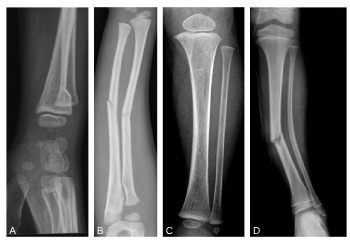

Le squelette pédiatrique est un squelette en croissance, possédant des propriétés de plasticité et de remodelage spécifiques. Le cartilage de croissance, ou physe, représente par ailleurs une zone particulièrement fragile dont l’atteinte peut entraîner des préjudices sévères sur la croissance et/ou l’axe d’un membre. Ces particularités physiologiques expliquent les lésions traumatiques propres à l’enfant que sont les fractures diaphysaires incomplètes (figure 115.1, A à D) et les fractures intéressant le cartilage de croissance (épiphysométaphysaires) classées selon la classification de Salter et Harris (figure 115.2).

Fig. 115.1 Fracture en « motte de beurre » (A), en « bois vert » (B), en « cheveu » (C), en « bois vert » sur le tibia, incurvation traumatique plastique sur la fibula (D).

Source : CERF, CNEBMN, 2022.